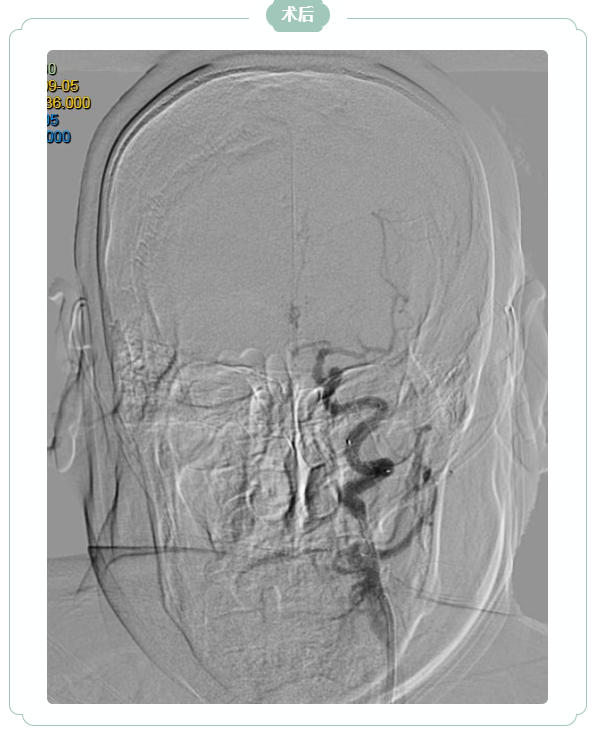

凭借丰富经验与先进介入技术,医生精准操控导管、导丝,克服重重障碍,历经2个多小时成功开通闭塞血管,并顺利植入一枚支架。术后第2天,韩大爷右侧肢体功能显著恢复,经过半个月综合治疗,目前已转入康复阶段,生活自理能力逐步提升。